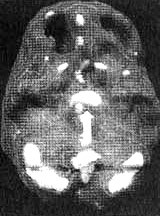

4. SPECT позволяет проводить дифференциальную диагностику состояний со сходной симптоматикой. Я познакомился с Маргарет, когда ей было 68. Выглядела она неухоженно и неопрятно. Маргарет жила одна, и ее близких это очень беспокоило, так как у нее появились симптомы тяжелой деменции. После того как она чуть не сожгла дом, оставив включенной плиту, ее поместили в психиатрическую клинику, где в то время работал я. Из общения с ее близкими обнаружилось, что Маргарет часто забывала, как зовут ее собственных детей, и нередко, ведя машину, сбивалась с дороги и оказывалась в незнакомом месте. Водительские навыки ухудшились настолько, что после четырех небольших ДТП всёго за шесть месяцев у нее отобрали права. К тому времени, когда я встретился с ее близкими, многих из них эта ситуация уже утомила, и они были готовы сдать Маргарет в специализированный приют. Другие были против такого решения и хотели бы сначала обследовать ее в условиях стационара. На первый взгляд казалось, что Маргарет страдает болезнью Альцгеймера. Однако по результатам SPECT обнаружилось, что активность мозга в париетальных и височных долях не нарушена. Если бы у нее был синдром Альцгеймера, кровоток в этих областях должен был бы быть снижен. Вместо этого единственной патологией, которую нам удалось обнаружить на снимках SPECT, стала зона повышенной активности в глубокой лимбической области в центре мозга. Такая картина часто наблюдается у пациентов, страдающих депрессией. Из-за схожей симптоматики у больных старшего возраста нередко бывает трудно дифференцировать депрессию и болезнь Альцгеймера. Тем не менее при псевдодеменции (депрессии, которая выглядит как слабоумие) человек может выглядеть слабоумным, на самом деле таковым не являясь. Это чрезвычайно важный момент, так как, диагностировав болезнь Альцгеймера, мы даем близким ряд специальных рекомендаций и назначаем пациенту некоторые медикаментозные средства. Между тем, диагностируя депрессию, мы проводим агрессивную медикаментозную терапию антидепрессантами в сочетании с психотерапией. Результаты обследования Маргарет убедили меня в том, что ей следует назначить антидепрессант Wellbutrin (бупропион). Всего три недели спустя она уже была разговорчивой, ухоженной и охотно общалась с другими пациентами. Через месяц после госпитализации ее выписали домой. Перед выпиской она попросила меня написать письмо в автоинспекцию с просьбой вернуть ей водительские права. Поскольку мы с ней ездим по одному и тому же шоссе, я заколебался. Я сказал ей, что, если улучшение будет стойким и сохранится на протяжении по меньшей мере полугода, а сама она станет придерживаться рекомендаций врача и принимать все лекарства, я напишу письмо в автоинспекцию. Через полгода она оставалась в хорошей форме. Я сделал повторный SPECT — результаты показали полную норму. Тогда я обратился в автоинспекцию, и ей вернули права.

Мозг Маргарет — псевдодеменция

Трехмерное изображение снизу — активный мозг, до лечения.

Трехмерное изображение снизу активный мозг, после лечения.